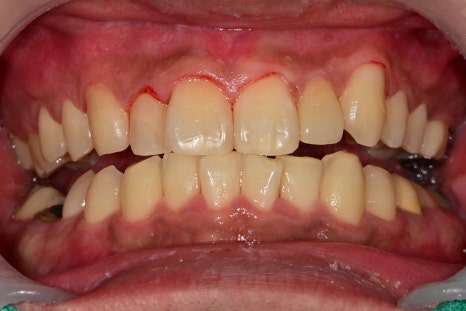

잇몸치료가 전 / 후를 비교해 보면

주변 잇몸들은 초진 시 관찰되었던

붉게 부어있던 부분들이 정상적인 핑크빛 잇몸이 되어있는 것을 확인할 수 있습니다.

충치치료는 완료가 되었지만

앞으로 플라그(치태)관리가 미흡할 경우

다시 2차 충치가 생길 가능성이 높기 때문에

정기검진이 치료보다 훨씬 중요하다고 말씀드립니다.